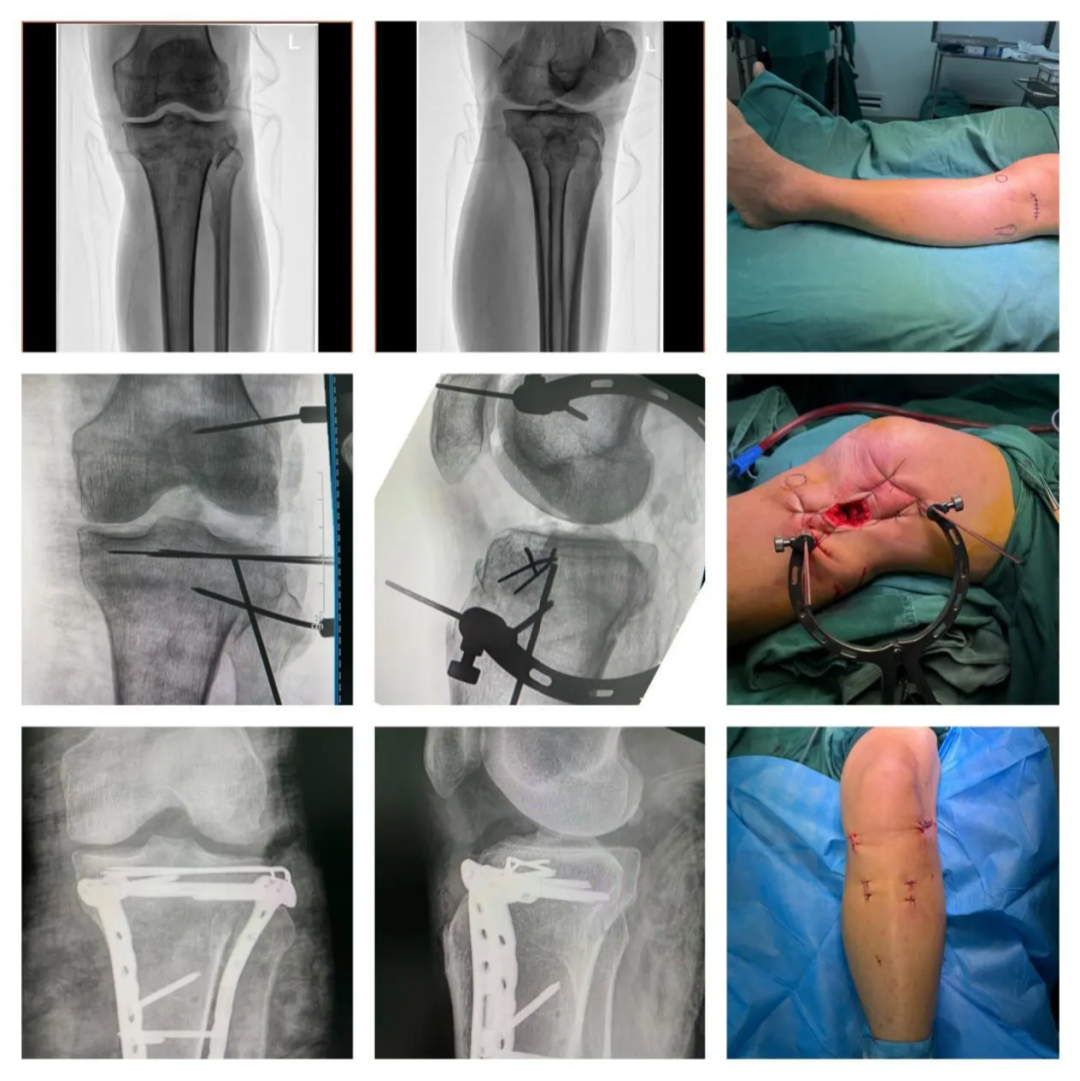

2.Case.02:28 岁,男性。右胫骨平台骨折(Schatzker II 型)合并胫骨髁间棘骨折